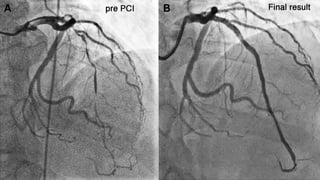

Coronary angiography of occluded

vessel

Coronary angiography ofoccluded vessel